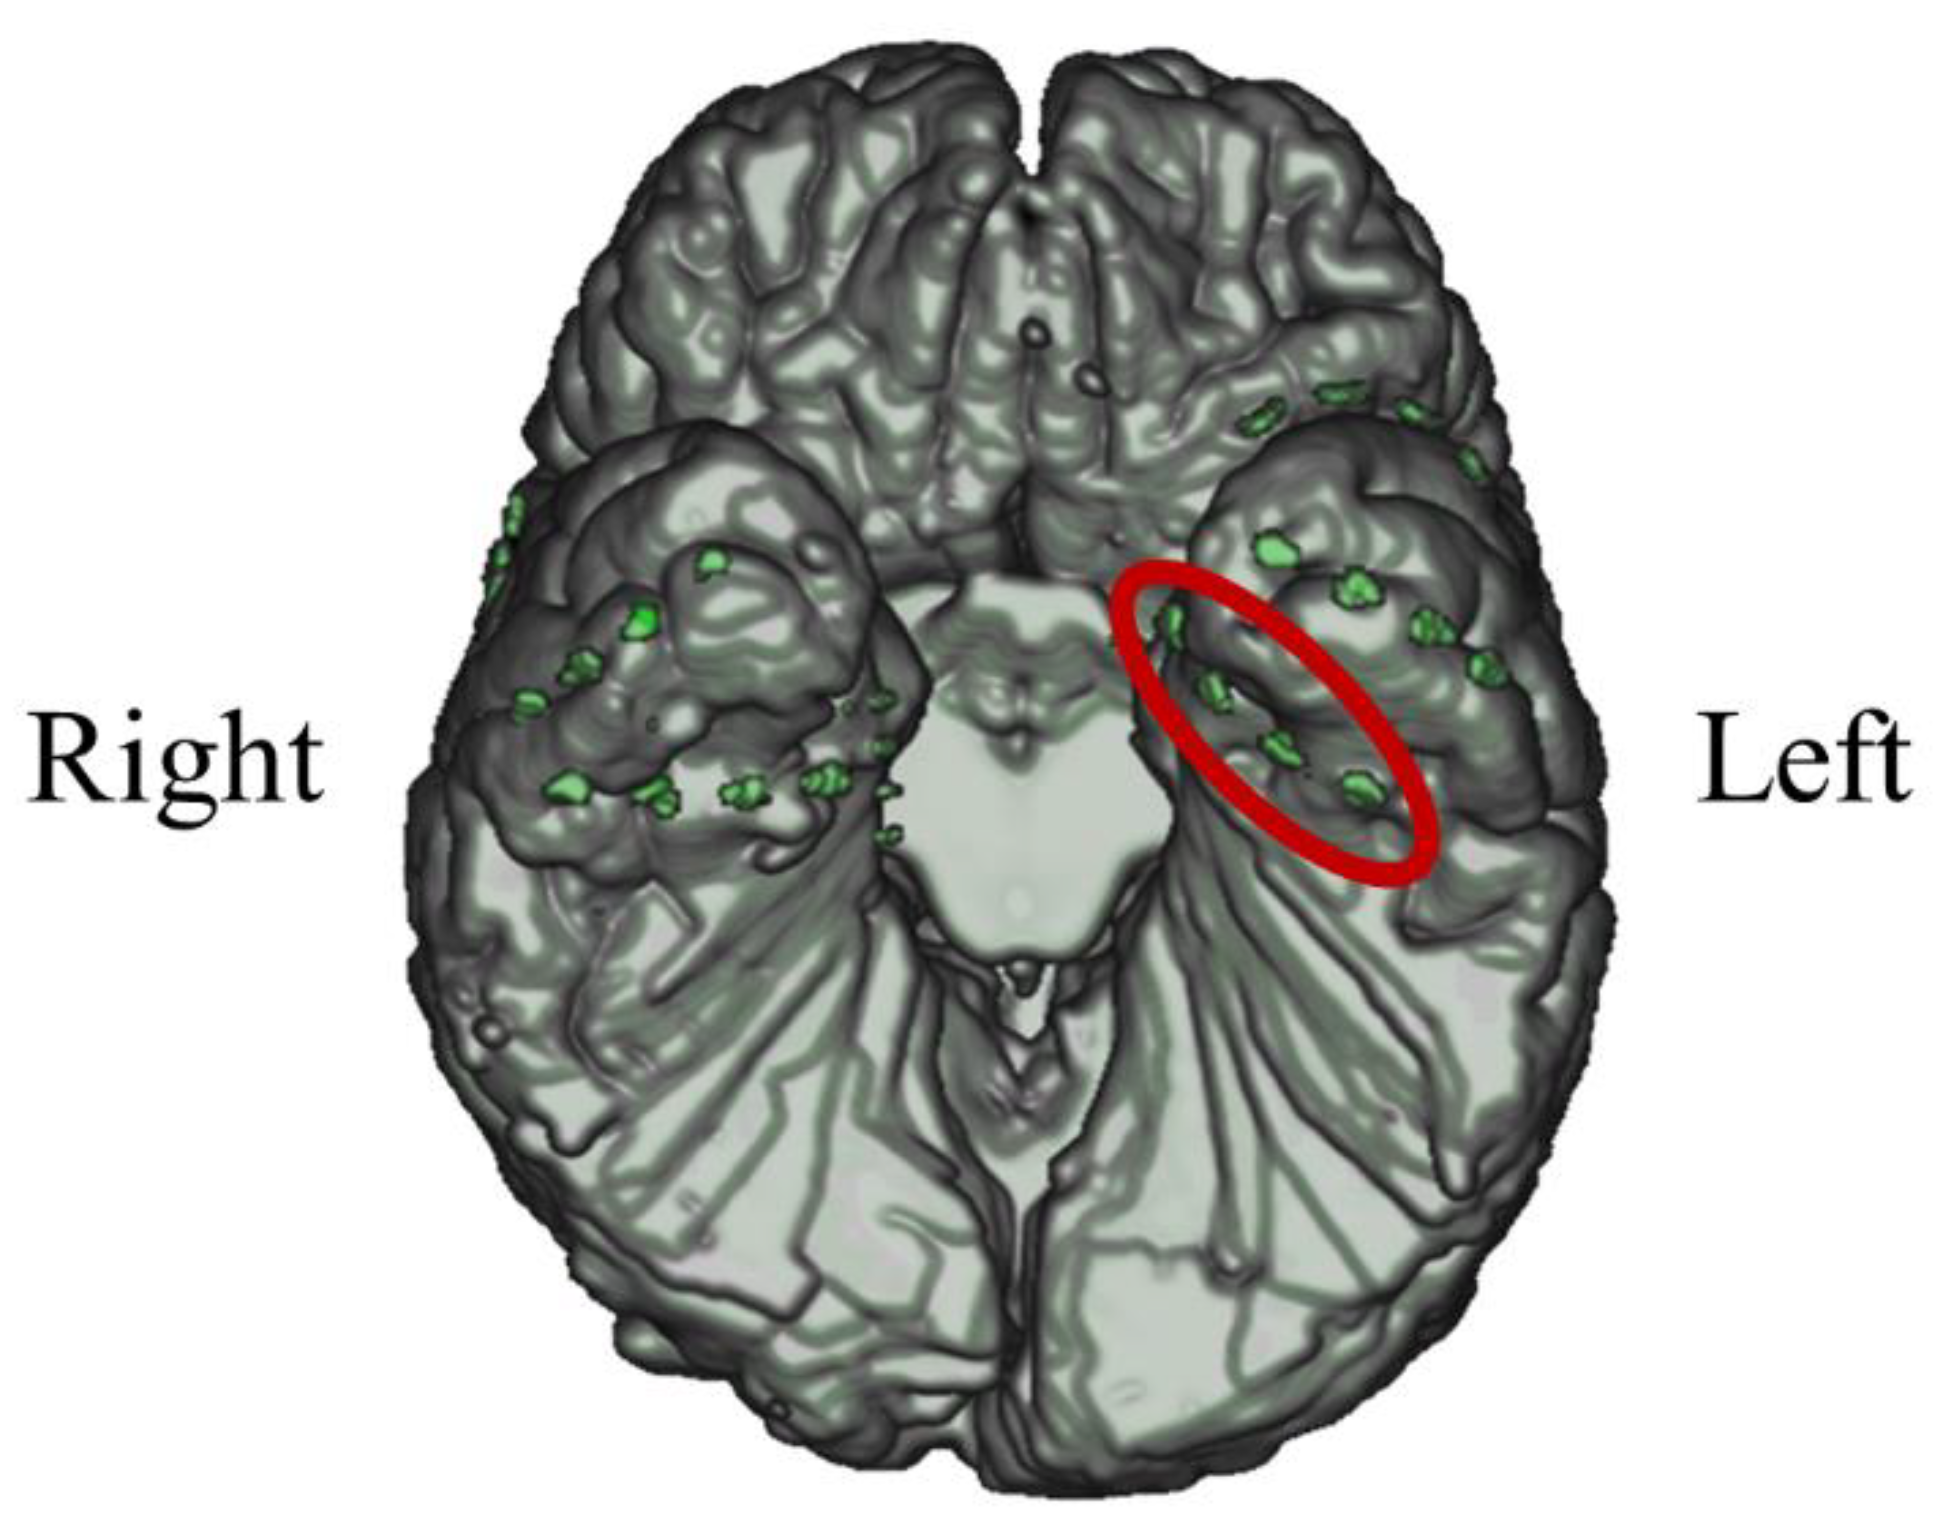

3.2.1. Intracranial Electrodes Used for Memory NF (P02)

In P02, subdural electrodes (Unique Medical, Tokyo, Japan) were implanted in the left MTL, covering the hippocampus. Four platinum electrodes (1.5mm in diameter) were longitudinally placed at 5mm intervals (centre to centre) along the left parahippocampal gyrus, and iEEG was measured and used for NF (Figure 12). A reference electrode placed on the dural side of the right temporal lobe was used for P02.